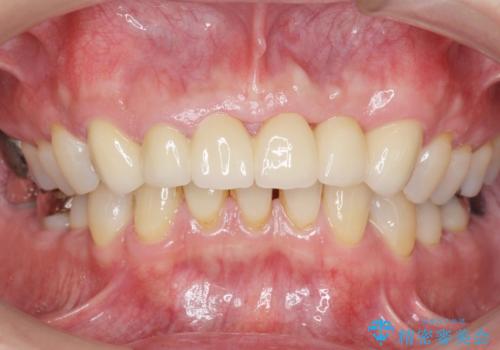

左上の側切歯(左上2)を抜去し、右上の側切歯(右上2)の再根管治療後、セラミックのブリッジによる補綴を行いました。

- ¥770,000 (根管治療×1本、土台×1本、仮歯×6本、クラウン×6本)費用は治療当時の料金となります

自然な仕上がりと咬み心地に大変ご満足頂けました。

「以前は出っ歯だったのにブリッジにしたことで歯並びもきれいになった!」と喜んで下さいました。

クラウンの種類:オールセラミッククラウン スタンダード